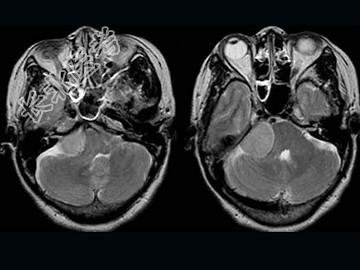

- 单项选择题女,57岁, 左侧听力进行性减退半年余,MRI检查如图, 最可能的诊断为 ( )

A、听神经瘤

B、三叉神经瘤

C、胆脂瘤

D、脑转移瘤

E、桥小脑角脑膜瘤